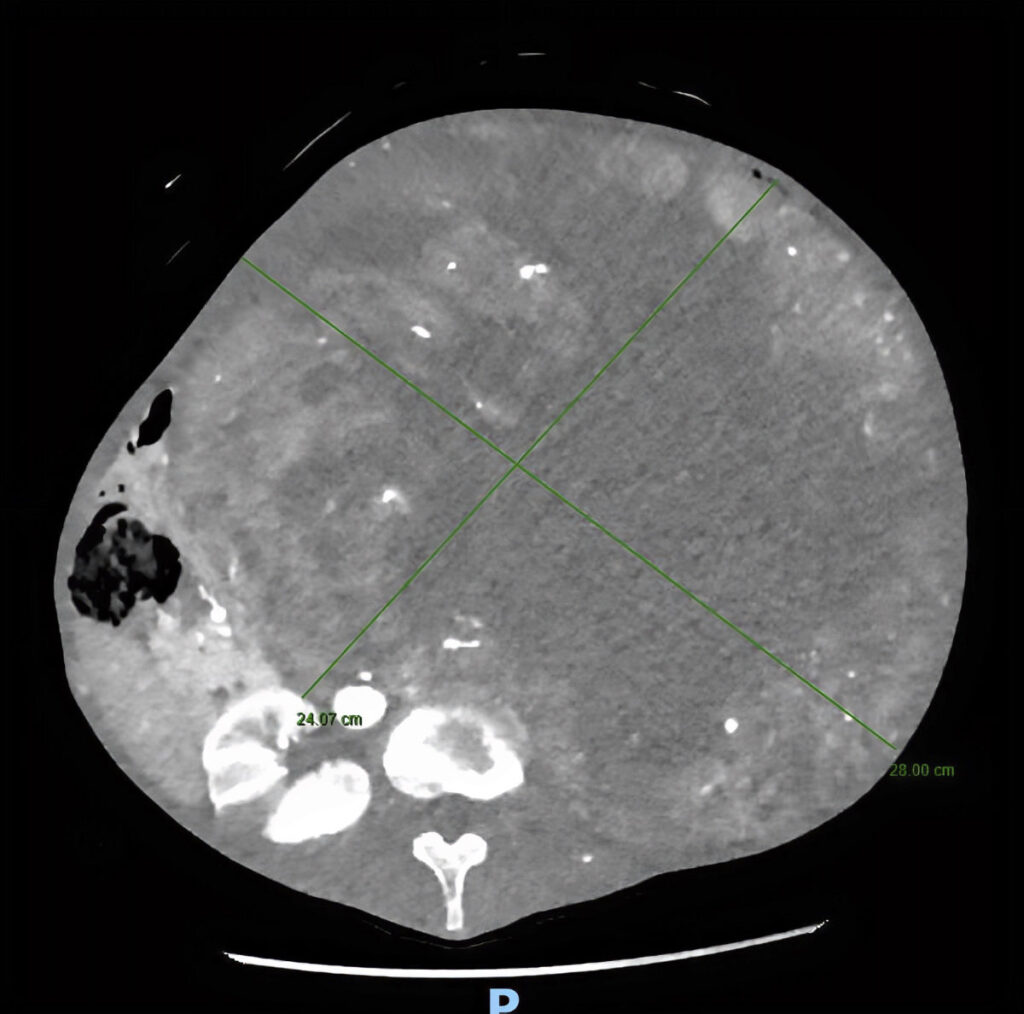

CAMPOBASSO – Un caso clinico ai limiti dell’incredibile è stato risolto nei giorni scorsi presso il P.O. Cardarelli di Campobasso. Un’équipe chirurgica d’eccellenza ha rimosso una gigantesca massa tumorale dal peso record di oltre 15 chilogrammi a una donna di 70 anni. Un intervento di altissima complessità che conferma il presidio molisano come punto di riferimento per la chirurgia oncologica d’urgenza e specialistica.

Tutto è iniziato da un disturbo apparentemente comune: la stipsi. La paziente si era infatti rivolta al Prof. Guido Sciaudone, Direttore della SC di Chirurgia Generale, per la risoluzione del problema. «Alla visita clinica è apparso evidente che il sintomo stipsi era secondario alla presenza di una voluminosa massa addominale», spiegano i medici. Gli accertamenti diagnostici hanno rivelato che la massa, paragonabile a un grosso cocomero, aveva origine dal rene sinistro e occupava l’intera cavità addominale, comprimendo intestino, fegato, milza, stomaco, pancreas e duodeno, oltre a compromettere la circolazione sanguigna.

L’operazione, delicatissima, ha previsto procedure integrate: la nefrectomia totale con asportazione del rene inglobato nella massa di verosimile natura eteroplastica (in attesa dell’esame istologico definitivo), la colectomia subtotale per rimuovere gran parte del colon ischemico a causa dell’occlusione cronica e della sofferenza vascolare, e il confezionamento di una derivazione intestinale esterna per permettere la canalizzazione.